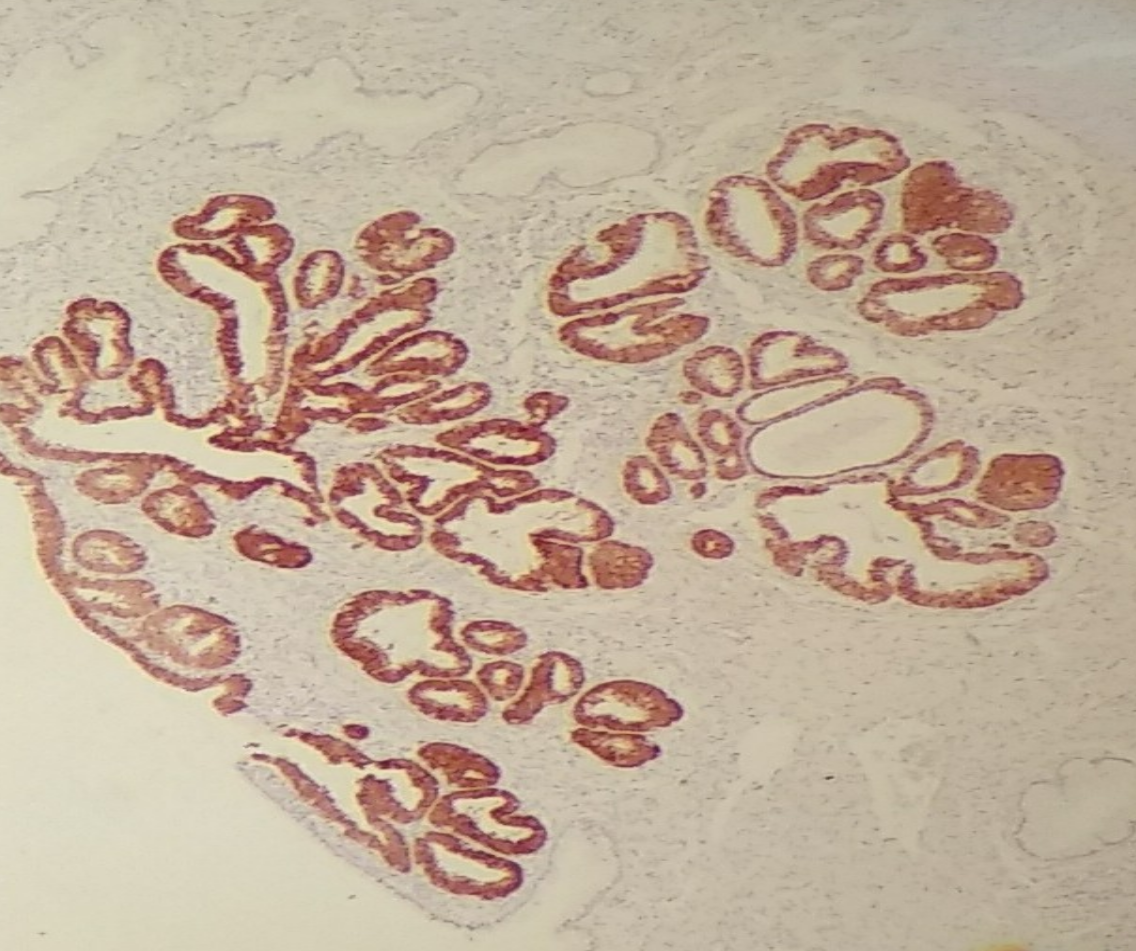

2 - Además del estudio convencional, consultas intraoperatorias o extemporaneas, realizamos otras técnicas de inmunohistoquimica y biología molecular (tipificación viral de HPV por técnica HPV DIRECT FLOW CHIP)

El sistema de HPV Direct Flow CHIP permite la detección del virus HPV y el genotipado de los 36 tipos de HPV de alto y bajo riesgo. Este sistema no requiere extracción previa de ADN sino que se procede directamente a la amplificación de las diferentes muestras tomadas por el equipo de salud. Esto permite reducir el tiempo de manipulación y obtención de resultados.

Los tipos de muestra son: tejido en parafina.